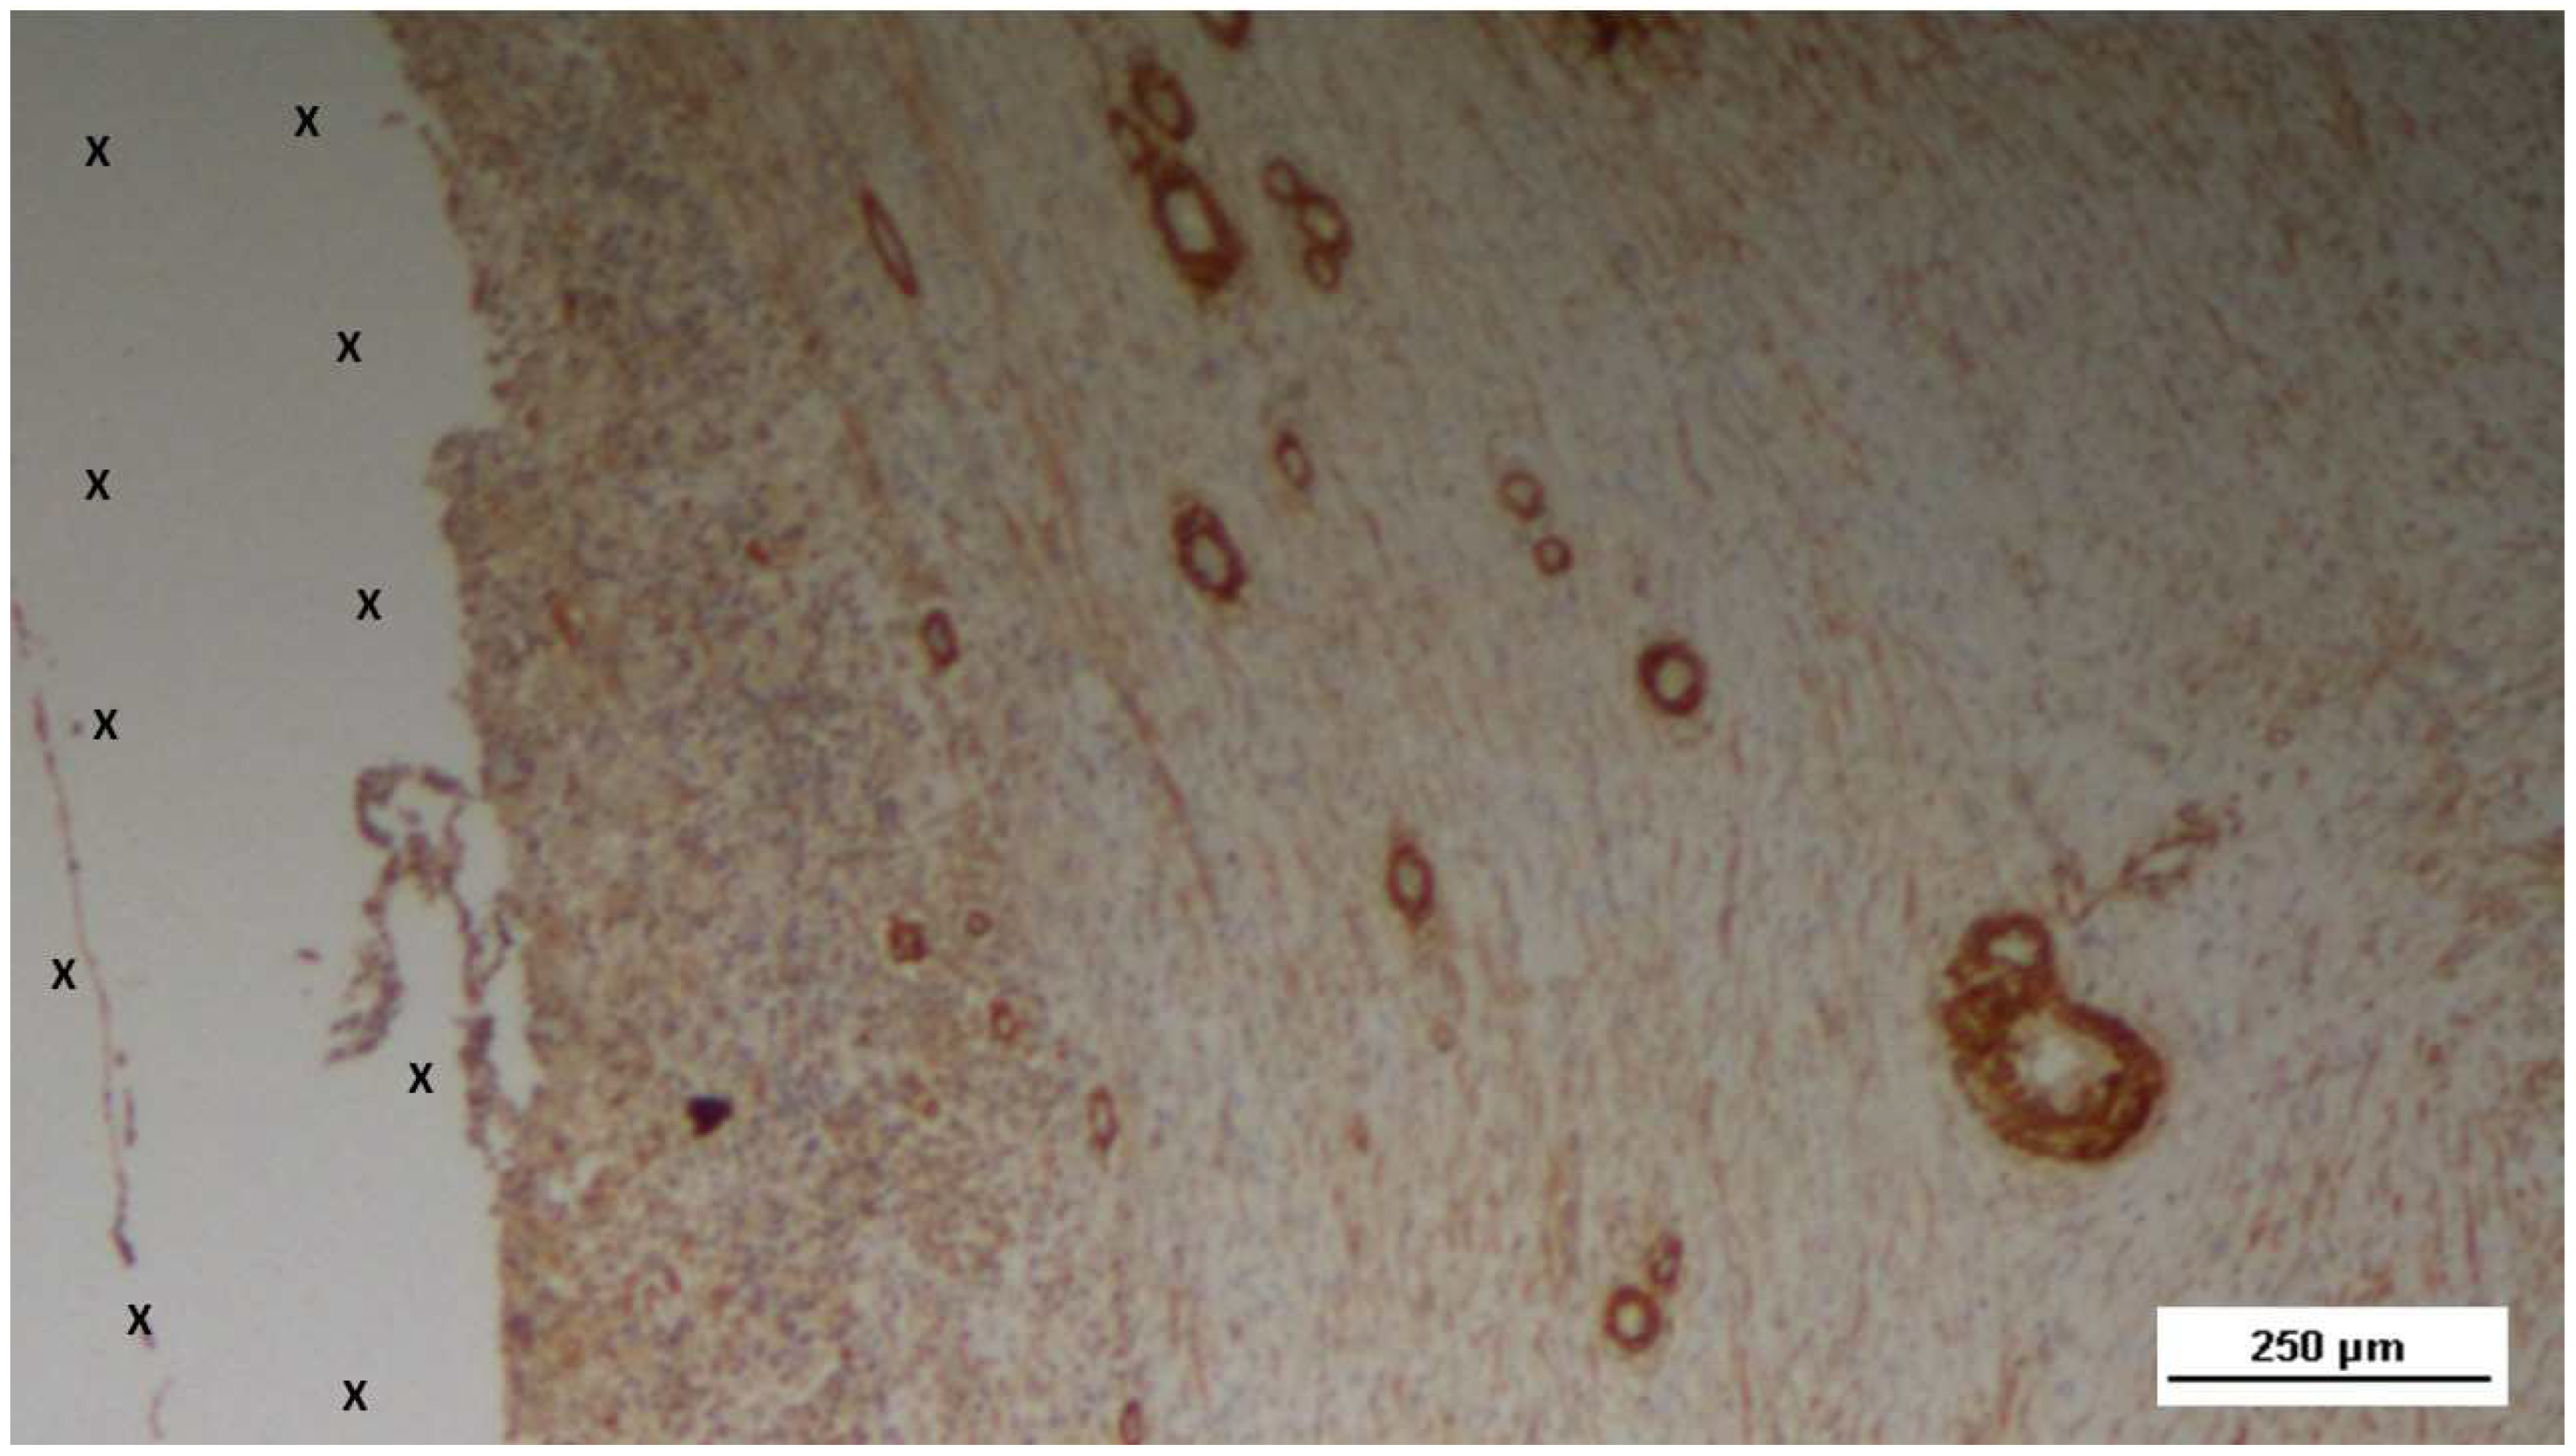

At the midterm (MT) stage, biopsy samples exhibited a notable increase in the number of NGFRp75-positive elements (Figure 23). These elements were associated with the presence of numerous large, developing nerve structures, arranged within the scaffold in a well-organized connective tissue matrix. These nerve structures were surrounded by clearly formed myelin sheaths positioned adjacent to the S&S Hernia System’s structure (Figure 24).

Figure 23. Biopsy specimen excised 4 months post-implantation (Midterm - MT). NGFRp75-positive elements (brown staining) are evident near the fabric of the 3D scaffold (X). NGFRp75 50X.

Figure 24. Biopsy sample excised 5 months post-implantation (Midterm - MT). Two developing nerve elements (yellow circles) are observed near broad venous structures (*) and a midsized artery (yellow arrows) in proximity to the TPE scaffold. NSE 50X.